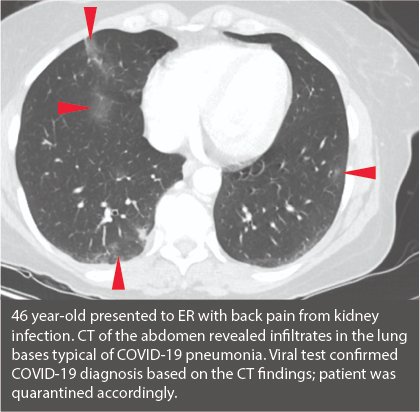

While #CT is not used as a first-line diagnostic test for #COVID19, #radiologists are finding "incidental" COVID pneumonia in asymptomatic patients.